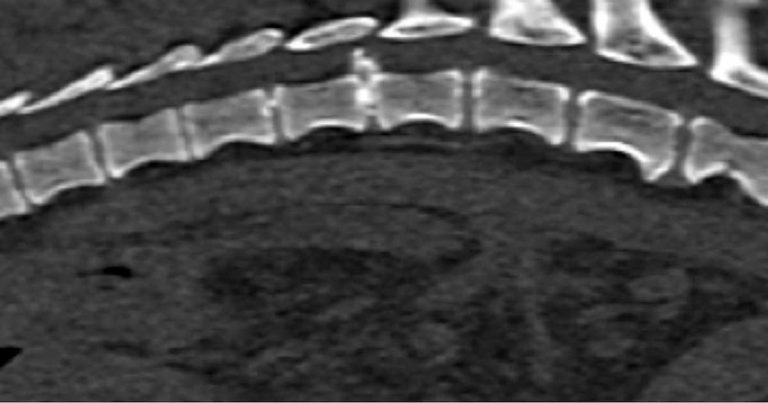

In chondrodystrophic dogs, but others as well, the nucleus pulposus undergoes a process of chondroid metaplasia, in which it is replaced by chondrocyte-like cells leading to calcification (Ghosh et al, 1977; Figures 1 to 3). This occurs typically before one year of age, whereas it is observed at an older age in non-chondrodystrophic breeds (Hansen et al, 2017).

Hansen type-one intervertebral disc herniation (Hansen, 1952) is caused by an acute herniation of the degenerated calcified nucleus pulposus through the annulus fibrosus (Figures 4 and 5).